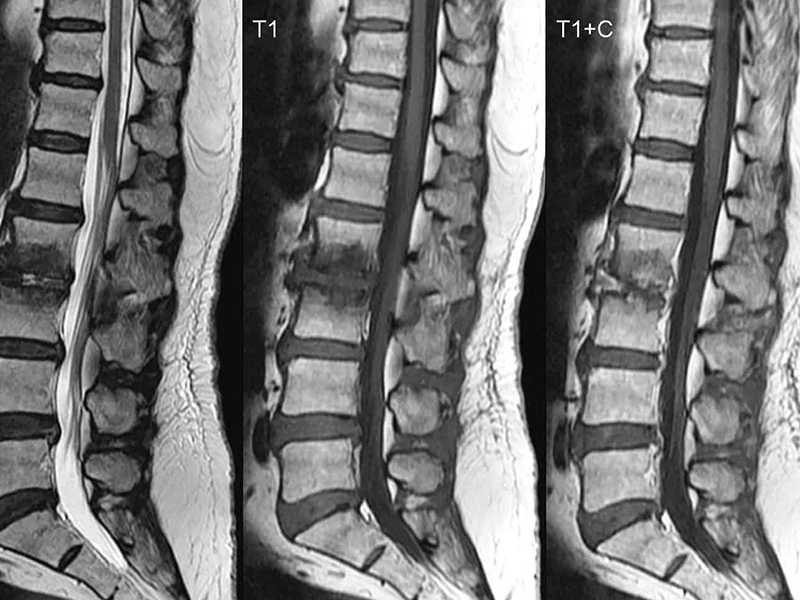

Boyun MR, ya da tıbbi adıyla servikal MR, boyun bölgesinin manyetik rezonans görüntüleme (MRG) tekniği kullanılarak ayrıntılı bir şekilde incelenmesidir. Bu yöntem, boyundaki kas, sinir, omurga ve disk yapılarını net bir şekilde gösterir.

Servikal MR, boyun bölgesindeki kemik, kas, sinir ve disk yapılarını detaylı bir şekilde incelemek için kullanılan ileri bir görüntüleme yöntemidir. Manyetik rezonans teknolojisiyle çalışan bu cihaz, güçlü manyetik alanlar ve radyo dalgaları yardımıyla vücudun iç yapısını görüntüler.

Boyun MR, boyun fıtığı, sinir sıkışması, tümörler, enfeksiyonlar, doğumsal anormallikler, omurilik hastalıkları ve travmatik yaralanmalar gibi durumların değerlendirilmesinde kullanılır. Ayrıca, baş ve boyun bölgesindeki damarsal problemleri, inflamatuar hastalıkları ve multipl skleroz gibi nörolojik hastalıkları teşhis etmek için de bu yöntem tercih edilir.

Servikal MR, özellikle boyun fıtığı, omurga daralması (spinal stenoz), omurilik ve sinir kökü tümörleri, multipl skleroz, disk dejenerasyonu ve travma sonrası yaralanmalar gibi hastalıkların teşhisinde kullanılır. Ayrıca, boyun bölgesindeki enfeksiyonlar, inflamasyonlar ve doğumsal anormallikler de bu yöntemle saptanabilir.